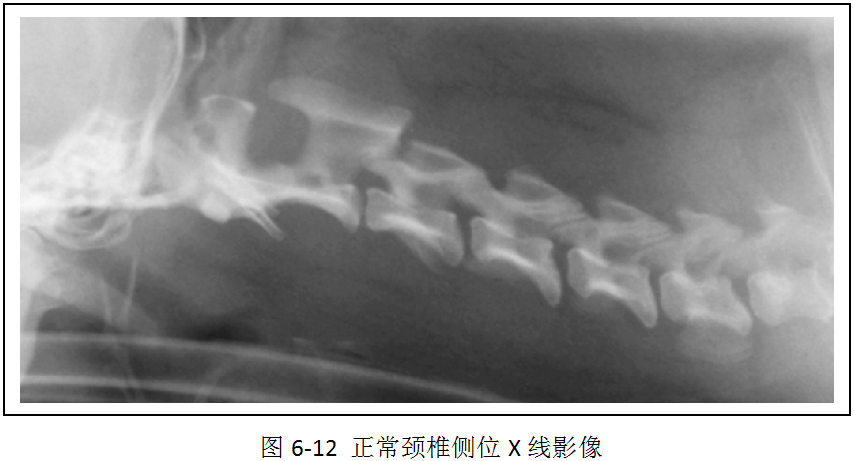

(2)识别X线影像中的颈椎、胸椎、腰椎和荐椎,并能确定属于位置(图6-12、图6-13)。

(3)识别椎间隙、椎间孔、棘突、横突的X线影像(图6-12、6-13)。

犬椎体侧位投照显示似方形,多数脊椎可显示椎弓、椎管的背侧缘与腹侧缘、椎体前后端骨骺、棘突、横突和椎体。猫的椎体较长,侧位显示似长方形,椎弓根、关节突欠清楚,椎间孔背侧缘不如犬易见。棘突在腹背位投照时呈致密狭长的断面高密度阴影。侧位投照时,相连椎骨的大小、形状和密度大致相同。第2颈椎棘突靠近第1颈椎椎弓,或与之重叠。第6颈椎横突宽大,呈翼状。胸椎椎体长度略比颈椎椎体短。第11胸椎棘突垂直向上,称为直椎。直椎之前的胸椎棘突斜向后上方,而直椎以后的胸腰椎棘突则斜向前上方。后段4~5节胸椎的的关节后突下方、椎间孔的前上界处,可显示一细小、类三角形的副突阴影。